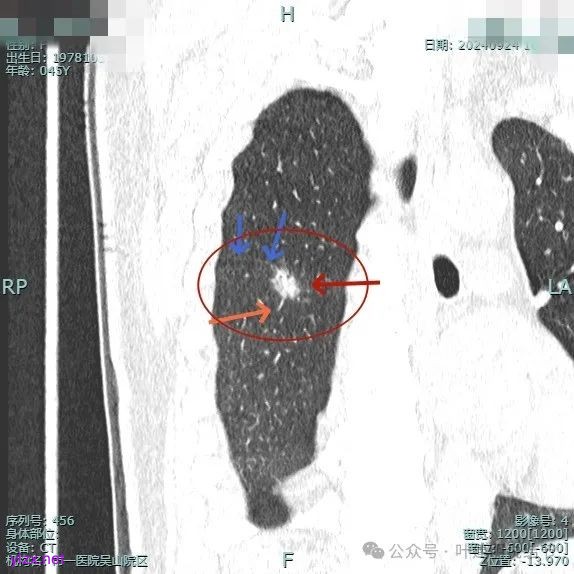

病灶2:

右中叶内侧段可见混合密度结节,大部分实性,形态与下叶背段的类似。

在门诊时我查了CT后认为大概率恶性,建议其入院手术,结友也办理了入院手续,准备接受手术治疗的。但入院后在术前我又仔细研究阅读她的影像,并分析靶重建图像,觉得右下背段病灶有的地方用恶性似乎不太好解释。

病灶1:

病灶是混合密度,边缘少许淡磨玻璃,灶内不太致密,表面不平,血管征有,但说不上明显异常增粗。

病灶紧贴叶间裂,而且感觉跨过肺叶,部分影响到上叶了,病灶本身密度虽实性为主,但是不太致密,有点松散的感觉。

总体实性部分密度较高,而磨玻璃部分密度较低,且瘤肺边界欠清,关键是跨叶间裂生长,这与肿瘤似乎不容易解释些。

毛刺有但不太锐利,磨玻璃有但偏淡,实性为但不太致密,叶间裂与之关系密切,病灶跨叶生长。

上图显得与肿瘤较为符合,但跨叶生长的话,侵袭力应该较强,可她这病灶较刚发现时进展并不太明显。

上图层面也较符合恶性,血管进入明显,有浅分叶的样子,整体觉得有一定收缩力与膨胀感。

病灶表面不平,混合密度,磨玻璃成分较淡。